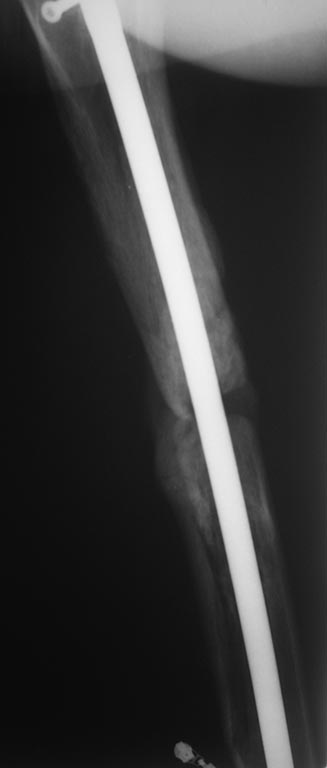

прилагаю). основной вопрос, тактический, чем лучше выполнить

реостеостеосинтез. У нас в наличии имеется: из штифтов Остеомед d-12мм,

старый набор Синтез с канюлированными штифтами максимальный d-14мм.,

пластины LC-DCP, аппарат Илизарова.

В плане 2 варианта: 1) удаление проксимальных блокирующих

винтов(сломаный тоже), фиксация бедра спице-стержневым аппаратом из 2-х

опор и компрессия в аппарате.

2)удаление металлоконструкции, и выполнение реостеосинтеза с

рассверливанием( учитывая очень широкий канал) с установкой винтов

поллеров в дистальном отломке. Жду ваших предложений и мнений. Спасибо